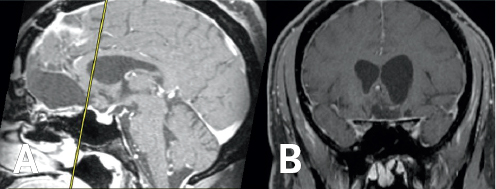

FIGURE 1.1 MRI demonstrating Robert’s olfactory groove meningioma. Sagittal (A) and coronal (B) images demonstrate a massive olfactory groove meningioma (yellow arrow) resulting in severe compression of the frontal lobe and vital optic structures required for vision.

(Left) Light and dark gray variations are enclosed by a large black and white outline. (Right) Light and dark gray variations are enclosed by a large black and dark gray outline.

FIGURE 1.3 MRI obtained one year following surgery. Post-operative sagittal (A) and coronal (B) MR images continue to demonstrate no evidence of residual or recurrent tumor.